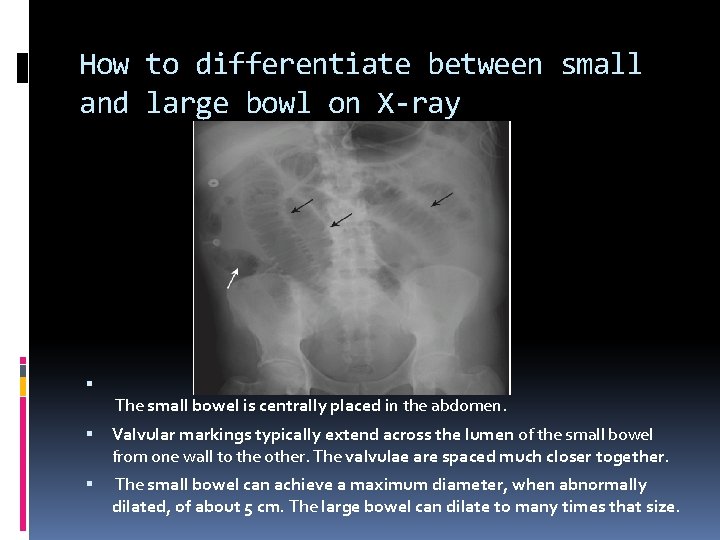

How to differentiate between small and large bowl on X-ray The small bowel is centrally placed in the abdomen. Valvular markings typically extend across the lumen of the small bowel from one wall to the other. The valvulae are spaced much closer together. The small bowel can achieve a maximum diameter, when abnormally dilated, of about 5 cm. The large bowel can dilate to many times that size.